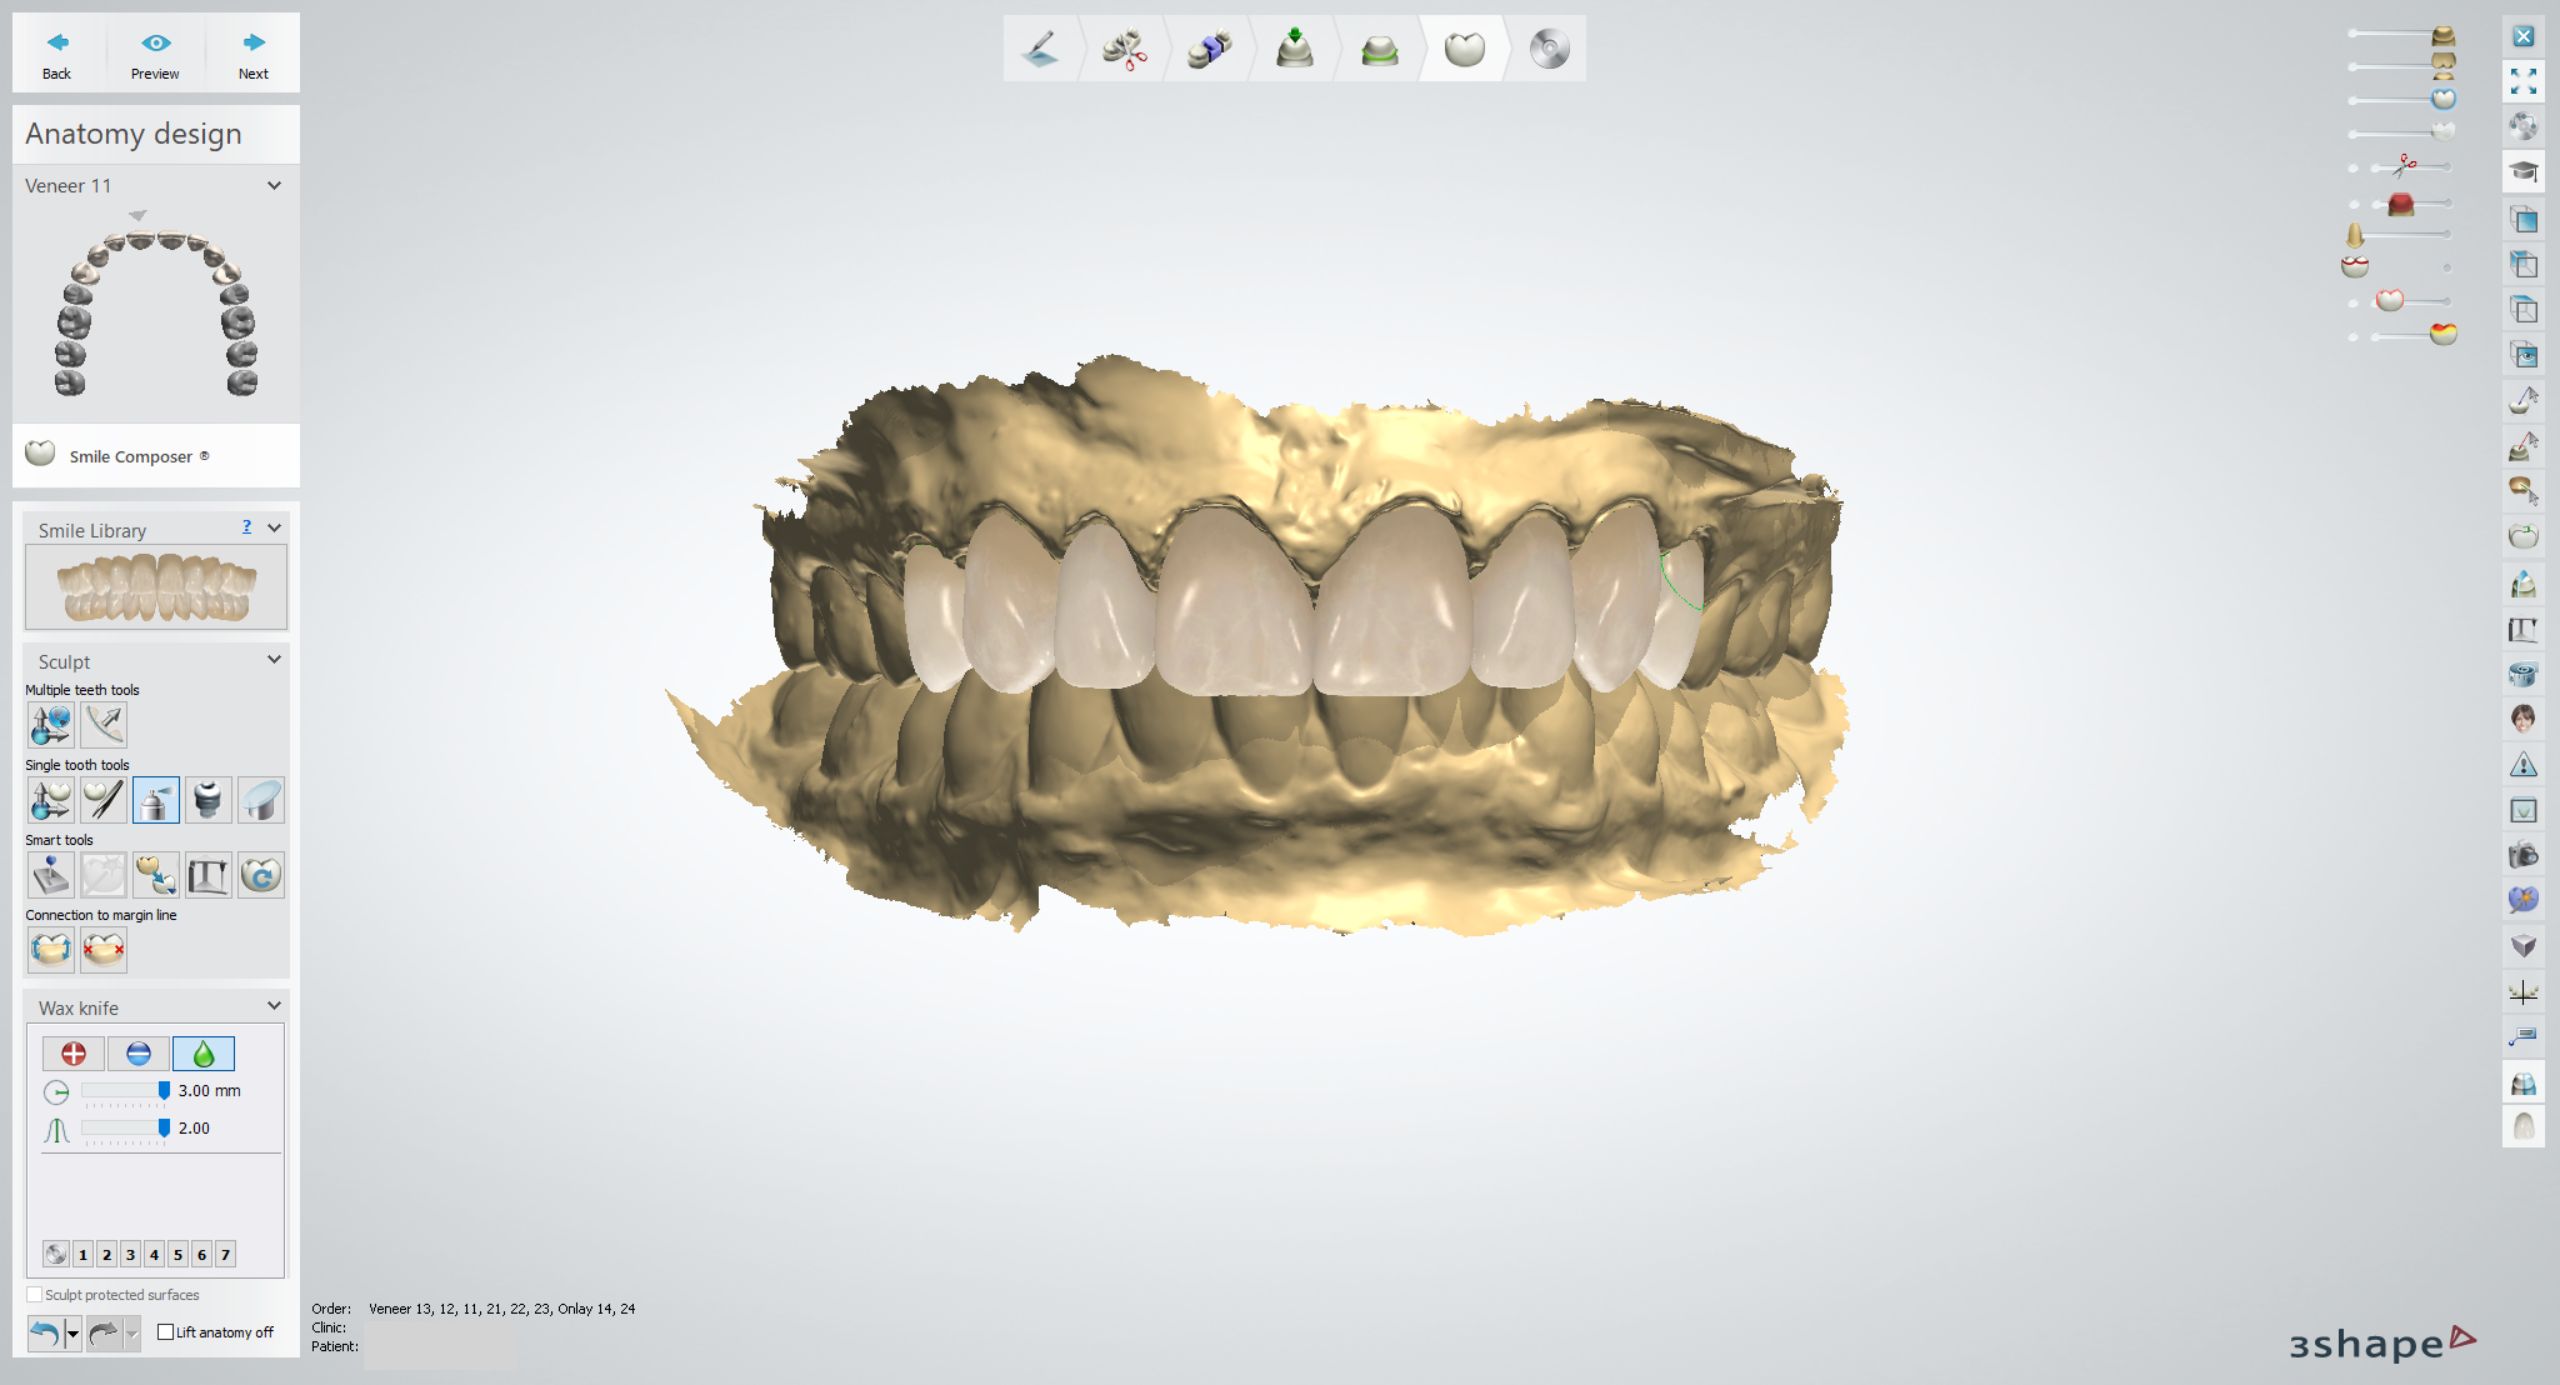

3shape Smile Design

Immerse yourself in the artistic beauty of 3shape Smile Design through substantial collections of inspiring images. blending traditional techniques with contemporary artistic interpretation. transforming ordinary subjects into extraordinary visual experiences. The 3shape Smile Design collection maintains consistent quality standards across all images. Ideal for artistic projects, creative designs, digital art, and innovative visual expressions All 3shape Smile Design images are available in high resolution with professional-grade quality, optimized for both digital and print applications, and include comprehensive metadata for easy organization and usage. Our 3shape Smile Design collection inspires creativity through unique compositions and artistic perspectives. Instant download capabilities enable immediate access to chosen 3shape Smile Design images. Our 3shape Smile Design database continuously expands with fresh, relevant content from skilled photographers. The 3shape Smile Design collection represents years of careful curation and professional standards. Diverse style options within the 3shape Smile Design collection suit various aesthetic preferences. Multiple resolution options ensure optimal performance across different platforms and applications. Professional licensing options accommodate both commercial and educational usage requirements. Each image in our 3shape Smile Design gallery undergoes rigorous quality assessment before inclusion. Time-saving browsing features help users locate ideal 3shape Smile Design images quickly. Advanced search capabilities make finding the perfect 3shape Smile Design image effortless and efficient.